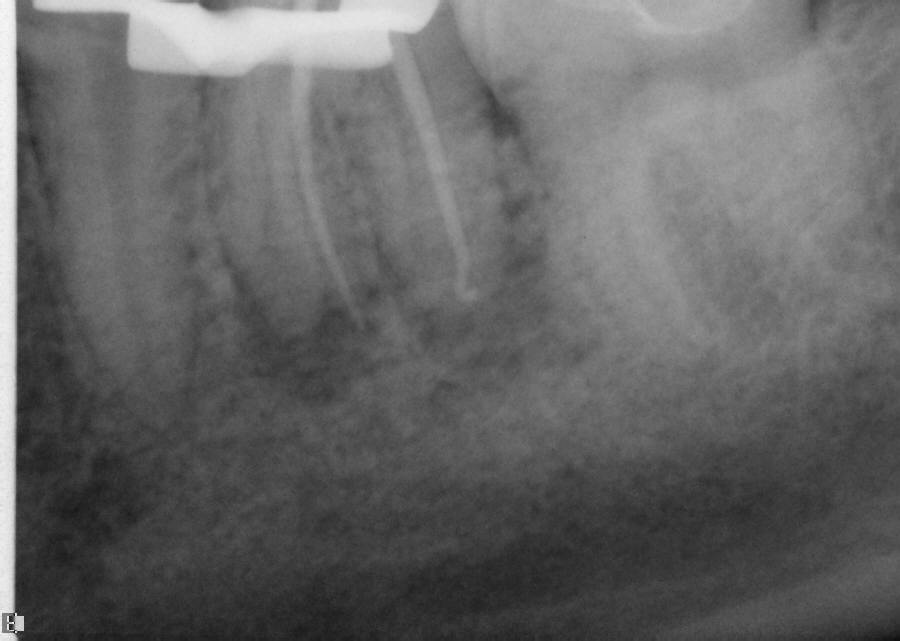

Excellent diagnosis essentially begins with two fundamental components: a doctor willing to listen to the patient’s chief complaint, and proper diagnostic tools. Among the most important tools are a precise periapical radiograph (PA) and bitewing (BW). Although a PA is often enough to provide an accurate portrayal of the patient’s condition, sometimes it alone does not suffice. Figure 1, Figure 2, and Figure 3 demonstrate a case that illustrates this point clearly. Despite two acceptable PAs (Figure 1 and Figure 2), it is difficult to assess the source of the patient’s pain to temperature. However, the BW radiograph Figure 3 provides significantly more clarity than either of the two PAs. The BW depicts localized bone loss (around tooth No. 2), a pulp stone (No. 2), a flat occlusion, numerous calcified canals, multiple restorations in tooth No. 30, and gross decay especially on tooth No. 3, which is the source of the patient’s pain to temperature. In this instance these images depict how much more useful a BW can be than just a conventional PA.

Fig 12. Working PA depicting arduous mesial bends and two mesial canals.

Figure 12